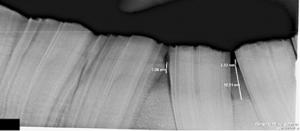

No! Teeth are living organs, and not blocks of ivory. Aggressive floating with power instrumentation can injure teeth, causing them to die slowly and painfully. It may take several years before the teeth shows signs of infection. While horse teeth erupt into the mouth over the life of the horse, each tooth has a limited lifespan. Aggressive floating removes excessive tooth crown unnecessarily, shortens the functional life of the tooth, and thereby shortens the lifespan of the horse.